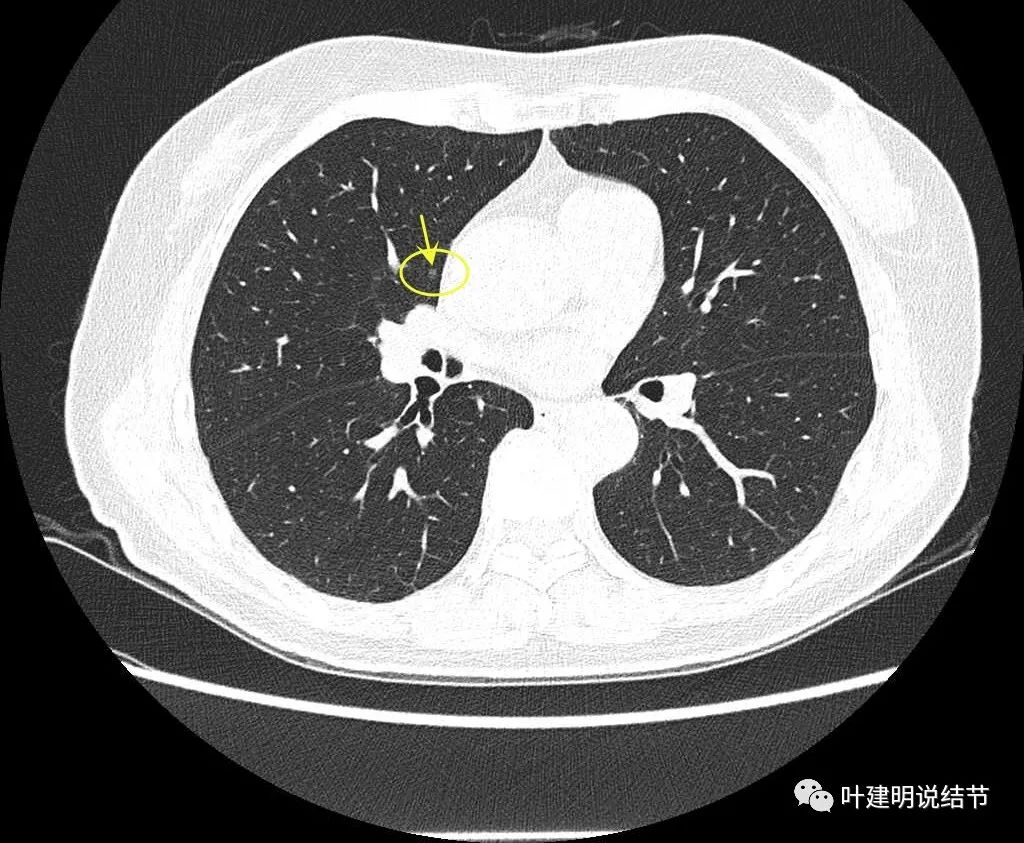

病灶9:右中叶实性结节,密度过高,小而实的结节以良性可能性大。

我们手术前做了靶扫描的重建,但当时请影像做的是病灶2、病灶6和病灶8。我的纠结在于中叶这个实性病灶是什么?如果它是炎性的或肺内淋巴结,密度是不是要更高一点?两肺这么多结节都考虑肿瘤范畴,只有这处是炎性或良性的,好像说不大通。我们以前也一直强调:如果多发结节,有的良恶性难定,有的较为明确是恶性,那么难定的也很可能同样的恶性的;有的较为明确是炎性的,那么难定的这处也可能是炎性的,因为致病的因素是一样的。有了这个念头之后,再回头去看中叶的结节,怎么总觉得虽像实性,但不够密实。所以我打电话请影像科同事重新为她中叶这颗也靶重建一下看看细节信息。

病灶9的重建发现不是实性结节,而混合磨玻璃密度。绿色箭头示边上有磨玻璃成分,而且紫色箭头示边缘是毛糙的,红色箭头示整体轮廓是清的。

上图也显示病灶边缘毛糙,不光滑,与胶原结节、淋巴结等良性结节是不符合的。

影像再判断:

右肺中叶病灶9考虑是浸润性腺癌,比其他病灶风险都高,它应该是主病灶了。但鉴于两肺多发病灶基本上都考虑肿瘤范畴的,即使此灶考虑浸润性,但毕竟还小,也有磨玻璃成分,存在转移的概率极小,仍应该可以考虑妥协性的楔形切除。